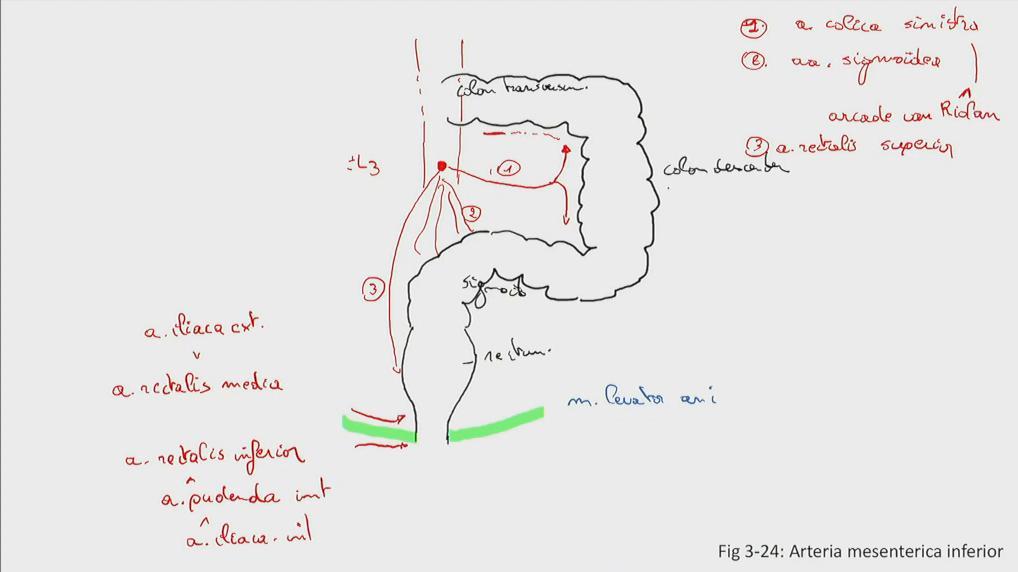

Fig 3.24: a. mesenterica inferior (AMI)

|